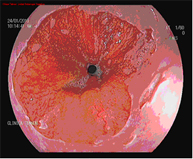

Radiofrecuencia con sistema HALO

El sistema Halo de radiofrecuencia es un aparato que permite la ablación de la mucosa esofágica hasta una profundidad de 1 mm de forma segura y uniforme. La ablación es una técnica en la que se calienta el tejido hasta que deja de ser viable o estar vivo. La tecnología HALO es un tipo muy específico de ablación en la que la energía calorífica se aplica de forma precisa y controlada. Los ensayos clínicos han demostrado que el tejido de Barrett se puede eliminar completamente con la tecnología de ablación HALO en el 98,4% de los pacientes.

Hay que hacer un seguimiento endoscópico y es probable que sea necesario repetir el tratamiento una o dos sesiones.